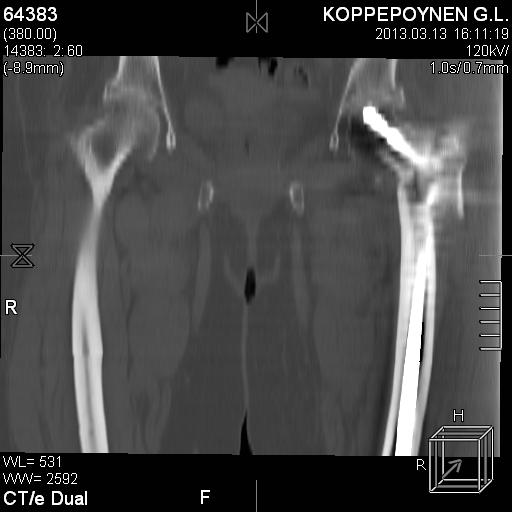

Делали КТ после операции.

есть КТ после операции. у пациентки направление введения стержня совпадает с направлением большого вертела, однако большой вертел расколот на 2 отломка. Задний отломок лежит по оси, передний отломом "отошел" и создается впечатление неправильного введения стержня. Динамизации у пациентки не было... Привезут снимки после операции, скину

Непонятно, на какой вопрос с помощью КТ хотели получить ответ? IMHO это было ненужное исследование, все проблемы были видны на обычном снимке. А что на второй проекции? Где аксиальная или профиль?